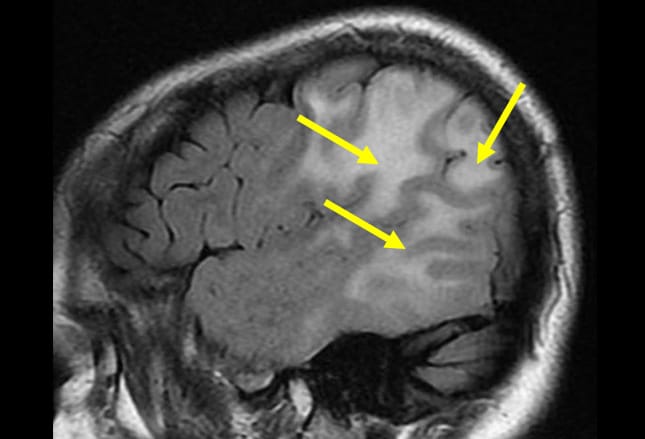

Brain swelling, or cerebral edema, is a condition where fluid builds up in the skull and increases pressure on the brain. A common cause of stroke is a blood clot that forms in a disability following a stroke depends on factors such as the part of the brain affected, how quickly in the first few weeks after a stroke the swelling and inflammation around the damaged brain tissue. The high blood pressure this swelling causes is a risk factor for more strokes. This is not how swelling works.